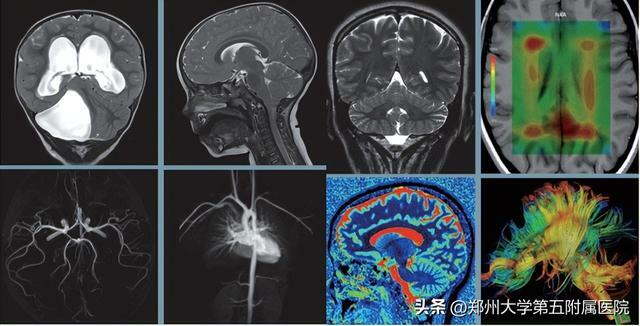

03MRI(核磁共振)

MRI使用較強大的磁場,使人體中所有水分子磁場的磁力線方向一致,這時磁共振機的磁場突然消失,身體中水分子的磁力線方向,突然恢復到原來隨意排列的狀態。簡單說就相當於用手搖一搖,讓水分子振動起來,再平靜下來,感受一下裡面的振動。根據質子在不同化合物中的信號差異,區分不同組織,包括腫瘤組織與正常組織。所以,核磁共振 (MRI)也被戲說為是搖搖看的檢查。

磁共振沒有輻射,但金屬物品在強磁場中會產生各種效應,危及受檢者安全並影響圖像質量,檢查前應予以去除。